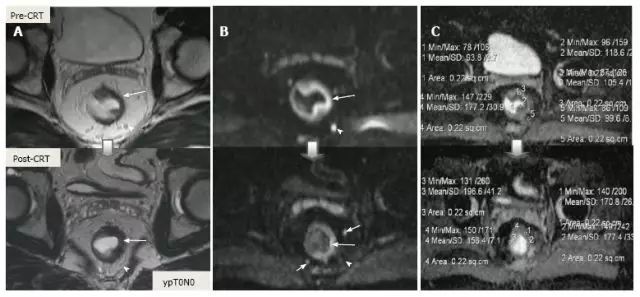

CRT 后淋巴结大小用于重新分期更可靠,放疗导致的正常淋巴结形态学变化使得转移淋巴结与正常淋巴结很难采用形态学和 DWI 相区分,经常导致淋巴结过度分期(图 24 和图 25)。

图片

图 24. DWI 对直肠癌放化疗后 ypT0N0 直肠系膜淋巴结评估假阳性。A. T2 加权轴位磁共振图像显示放化疗后结节大小明显减少,与阴性淋巴结(箭头)相符;B. DWI 图像,直肠周围淋巴结治疗后高弥散信号,与阳性淋巴结(箭头)相符。

图 25. DWI 成像,直肠癌放化疗后 ypT0N0 阳性直肠系膜淋巴结。A. T2 加权轴位图像显示淋巴结大小明显减少,与完全反应相符;B. 残余的纤维化淋巴结呈现高弥散信号强度,错误提示为转移性淋巴结(箭头)。